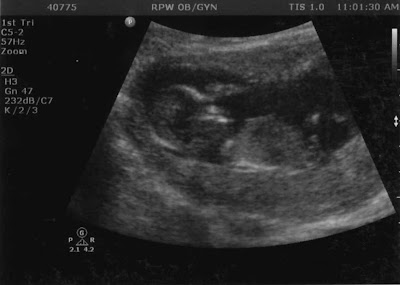

This is one of our Ultrasounds at 13 weeks and I am just shy of 14 weeks today. :)